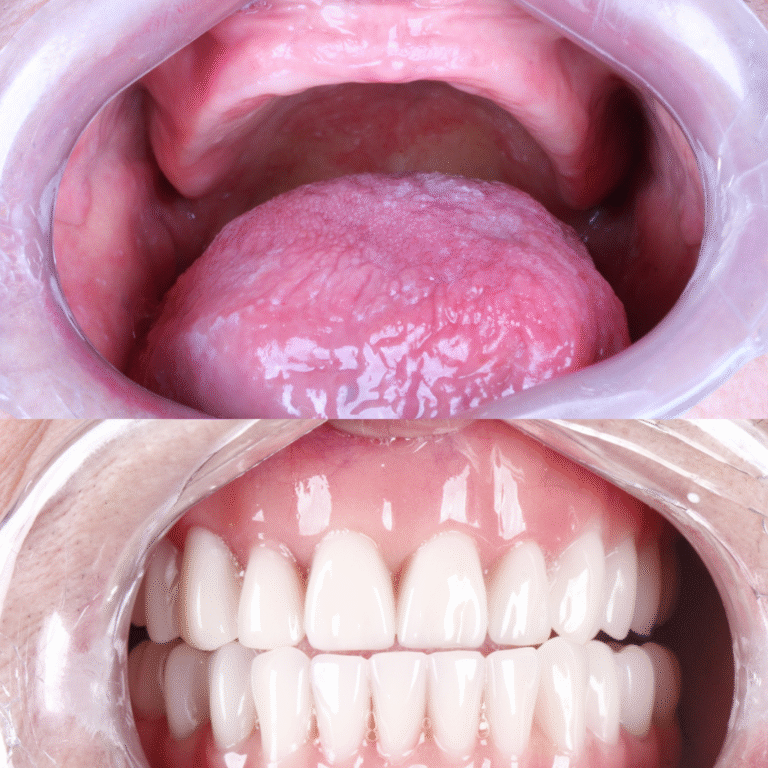

Veja alguns dos resultados obtidos através dos nossos tratamentos especializados.